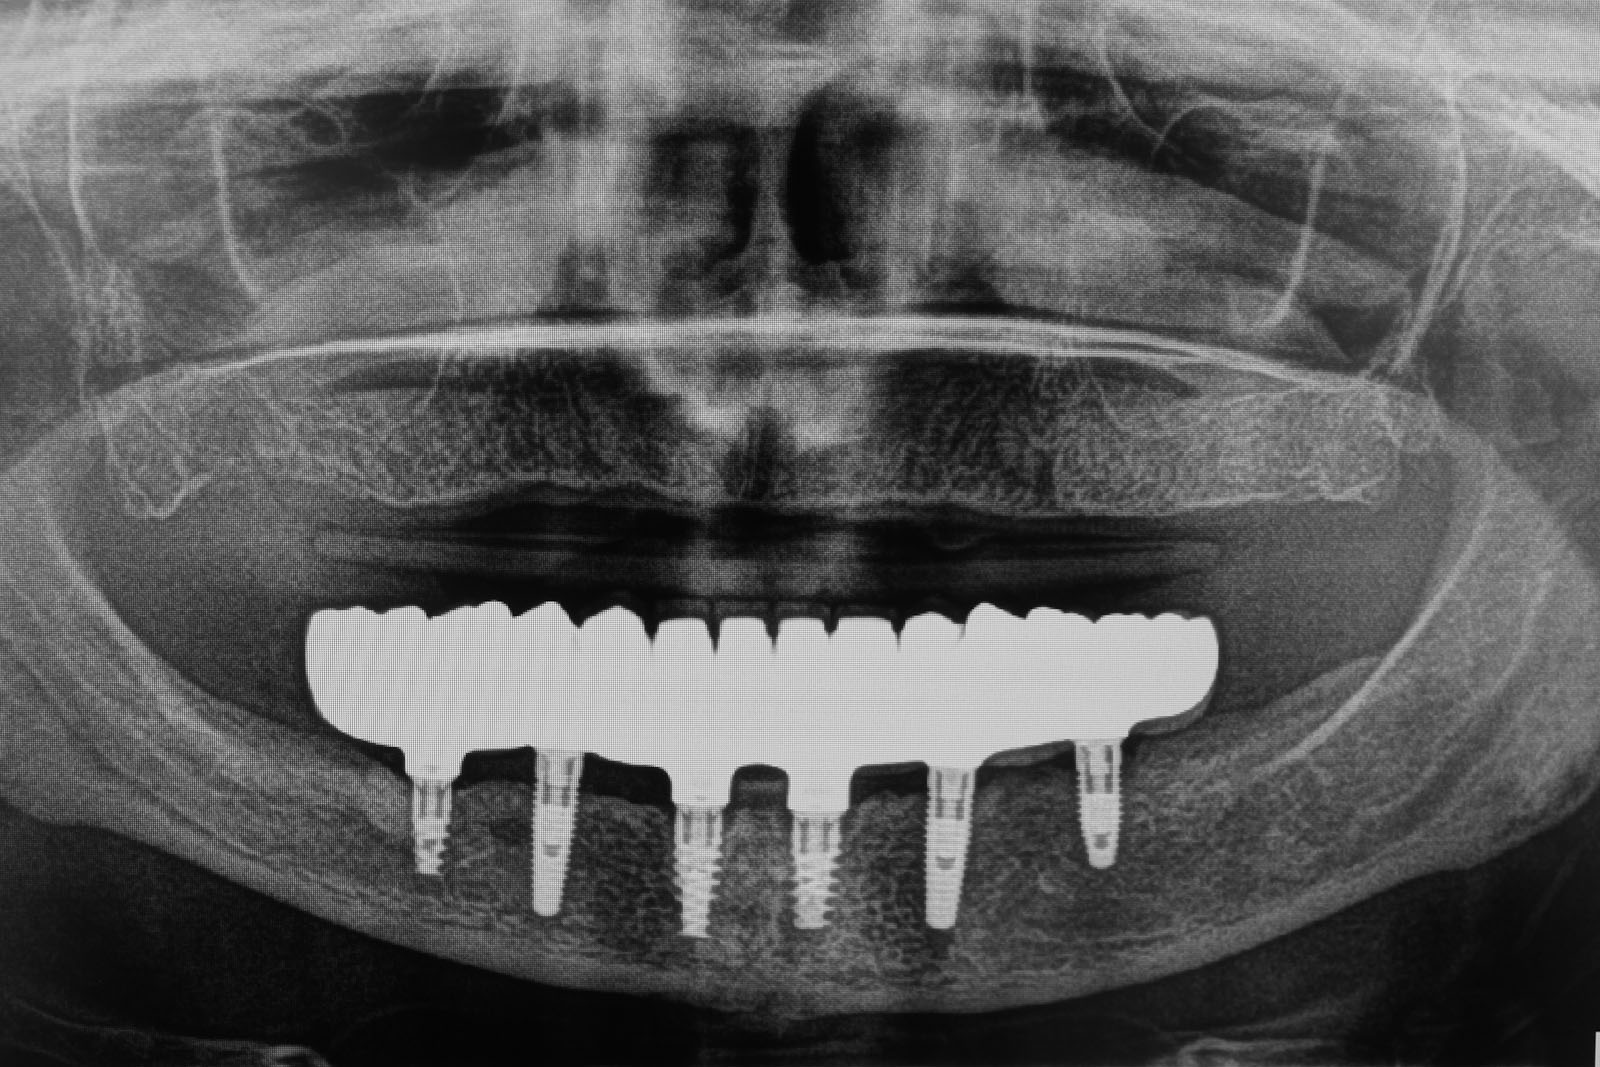

Nie ma takiej konieczności. Z biologicznego punktu widzenia jest to nawet niewskazane. Regułą i standardem w odbudowie protetycznej uzębienia jest rekonstrukcja górnego, jak i dolnego łuku zębowego od pierwszego trzonowca po stronie prawej do pierwszego zęba trzonowego po stronie lewej. W oparciu o diagnostykę obrazową (OPG, CBCT) standardowo oceniamy jakość i objętość kości oraz planujemy leczenie, bazując na prognozowanej ilości wszczepianych implantów. W zależności od zaplanowanych rozwiązań protetycznych ich ilość zwykle waha się od dwóch do dziesięciu implantów jako fundament dla rekonstrukcji uzębienia górnego lub dolnego łuku zębowego.

Jest to opatentowana metoda rekonstrukcji implanto-protetycznej kompletnego uzębienia stosowana przy bezzębiu zarówno dla dolnego, jak i górnego łuku zębowego. Bazuje na charakterystycznie wszczepionych 4 implantach zębowych, stąd nazwa Wszystko na 4. Dwa środkowe wprowadzane są w kość prostopadle do jej brzegu i równolegle do siebie, dwa boczne wszczepiane są pod kątem 45 stopni. Rozwiązanie protetyczne to most przykręcany na stałe do implantów, który może być zakładany natychmiast po zabiegu implantacji lub w czasie odroczonym. Gwarancją natychmiastowego przywrócenia funkcji żucia jest odpowiednia siła osadzania implantów mierzona dynamometrycznie w trakcie ich wszczepiania oraz należyta staranność wykonania i osadzenia prac protetycznych.

Opierając się na badaniu klinicznym pacjenta oraz diagnostyce obrazowej  (RTG, OPG oraz CBCT), jesteśmy w stanie przyjąć założenia co do zastosowania właściwej techniki preparacji kości przy implantacji, możliwości prawidłowego wykonania i zastosowania natychmiastowych protez, a tym samym możliwości wykonania zabiegu natychmiastowego obciążenia implantów. Ostatecznej oceny prawidłowej stabilizacji implantów dokonuje się podczas zabiegu operacyjnego.